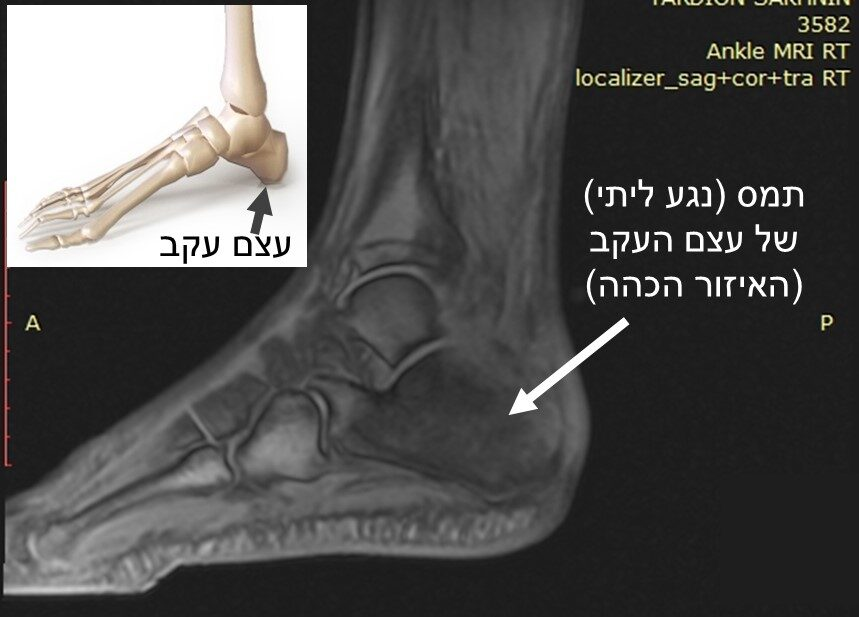

לאחר עוד 10 ימים יוסי נסע שוב לבית חולים, ושם נעשו בדיקות דימות מסוגים שונים שזיהו כי "העצם בעקב אכולה" (ראו בתמונה) אולם לא נתקבלה אבחנה ספציפית.

יוסי וזוגתו עברו בין מרכזים רפואיים ובדיקות דימות רבות, עד שהגיעו למומחה בבי"ח רמב"ם, יוסי: "הוא הראה לנו בצילום שהעצם אכולה כלפי פנים כך שבחלק מהעקב כבר לא רואים בכלל את העצם. הוא הראשון שאמר את זה "נגע ליתי" ואמר שזה למעשה סרטן [עצמות]"

סמדר: "הוא אמר שזה נגע ליתי, שזה מבחינתם סרטן של העצם. זה לא דבר שמתרפא מעצמו. שאלתי אותו: ד"ר, זה לא יכול לעבור לבד? הוא אמר שלא, ושזה תמיד מגיע לבסוף לכריתה של הרגל". הוא השווה שוב ושוב בין הצילומים שלפני כמה חודשים ושל עכשיו, ולא האמין. העצם השתקמה במלואה."

הקונפליקט הפוגע בעצמות הוא ירידת ערך עצמי חזקה, שבשלב בו הקונפליקט פעיל, מביאה לדלדול עצם (אוסטאופורוזיס) ואם עוצמתו גבוהה והוא נמשך זמן רב, הדבר מביא ל"נגע ליתי" (תמס עצם, אוסטיאוליזה), מצב בו מבנה העצם מתפרק ונעלם, ונוצרת מגרעת, או חור של ממש בעצם (שעדיין בתוך המעטפת שלה). ברפואה המקובלת תהליך זה נתפס כסרטן עצמות.